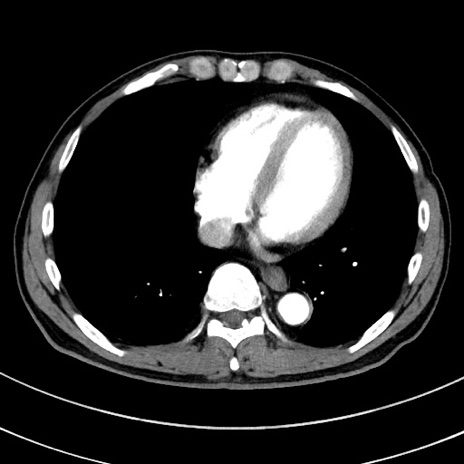

症例8(横断像)

【症例】 60歳代男性

【主訴】 黒色吐物

【現病歴】 4日前から嘔気自覚、2日前の朝食後にも嘔気あり、自分で手で嘔吐反射起こし嘔吐したところ血が混ざっていたため受診。

【既往歴】 5年前汎発性腹膜炎を伴う急性虫垂炎で手術、高血圧、前立腺肥大症、高脂血症

【身体所見】 腹部正中に手術癩痕あり 腹部平坦・軟圧痛なし膨満感あり

【データ】WBC 8400、CRP 4.54